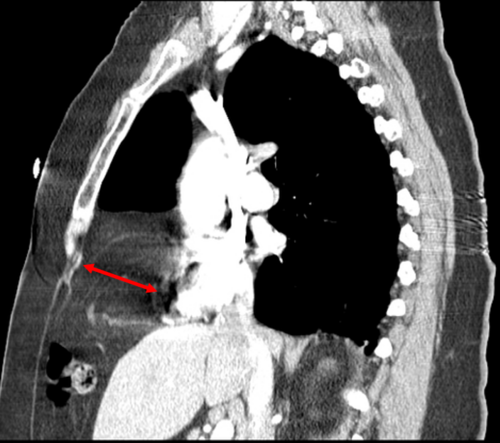

CT — Pulmonary Contusion (Annotated)

Axial CT showing pulmonary contusion with ground-glass opacification and consolidation following chest trauma

CT Downloaded 2026-03-15

Ct

Lung Window 120 kVp W:1500 L:-600

Wikimedia Commons: Pulmonary contusion CT arrow.jpg